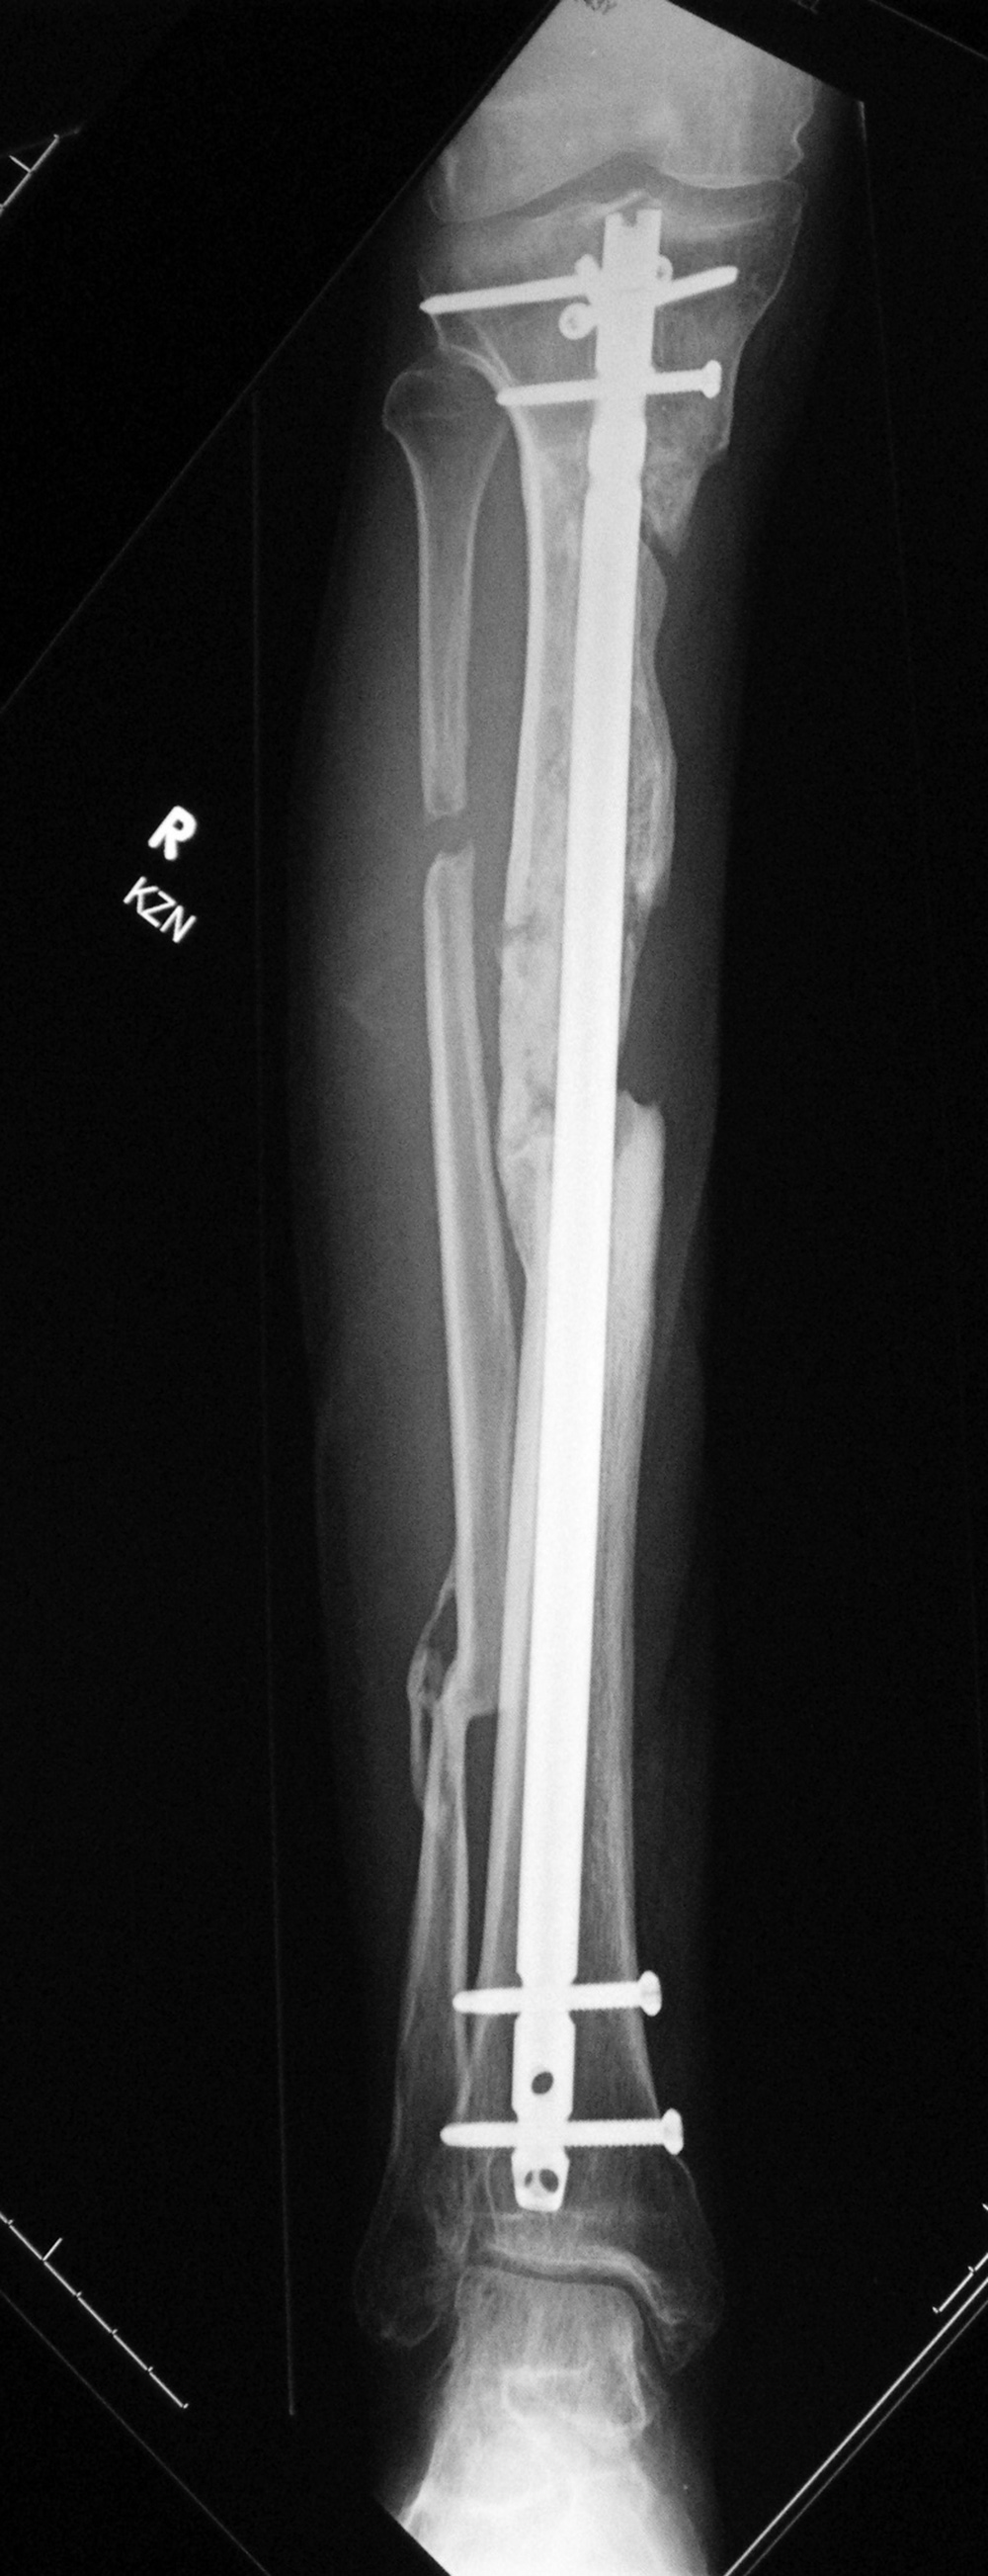

Right tibia fracture dynamization

Right tibia dynamization - before

Right tibia dynamization - after

43 year-old man with complex, healing right tibia and fibular fractures. There is an intramedullary rod (nail) in the right tibia. Four locking screws are present proximally and two distally. After dynamization the distal locking screws have been removed.